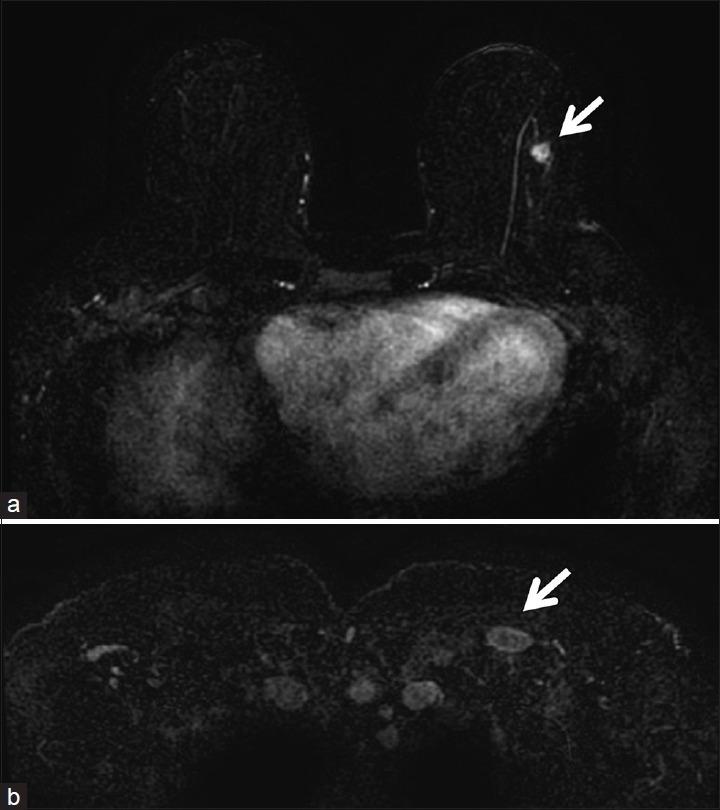

Metastatic tumors are rare in the breast. Well-differentiated neuroendocrine tumors (WDNETs) are slow-growing neoplasms that arise from neuroendocrine cells, particularly in the gastrointestinal tract and bronchial tree. Metastatic WDNET to the breast is a rare entity. We present a case report of ileal WDNET metastatic to the breast which was initially identified as a small mass in the patient's left breast on screening mammography. Targeted ultrasound identified a suspicious mass, and ultrasound-guided percutaneous core biopsy was performed. Pathology revealed metastatic WDNET. Breast magnetic resonance imaging (MRI) was then performed and demonstrated left axillary Level 2 lymphadenopathy, and liver lesions were suspicious for metastasis. The patient underwent abdominal computed tomography (CT) to evaluate for distant metastatic disease. A spiculated mass was found near the ileocecal valve, suggestive of primary ileal WDNET. In addition, CT identified multiple liver lesions, most compatible with metastasis. Indium 111 OctreoScan confirmed radiotracer uptake in the ileum consistent with primary neuroendocrine tumor. In this report, we review the imaging characteristics of metastatic WDNET to the breast by different imaging modalities including mammogram, ultrasound, and breast MRI.

转移性肿瘤在乳腺中较为罕见。高分化神经内分泌肿瘤(WDNETs)是起源于神经内分泌细胞的生长缓慢的肿瘤,尤其多见于胃肠道和支气管树。乳腺转移性WDNET是一种罕见的情况。我们报告一例回肠WDNET转移至乳腺的病例,该病例最初在乳腺钼靶筛查时被发现为患者左乳的一个小肿块。靶向超声检查发现一个可疑肿块,并进行了超声引导下经皮穿刺活检。病理结果显示为转移性WDNET。随后进行了乳腺磁共振成像(MRI)检查,结果显示左侧腋窝2级淋巴结肿大,肝脏病变可疑为转移灶。患者接受了腹部计算机断层扫描(CT)以评估远处转移情况。在回盲瓣附近发现一个有毛刺的肿块,提示原发性回肠WDNET。此外,CT检查发现多个肝脏病变,最符合转移表现。铟111奥曲肽扫描证实回肠有放射性示踪剂摄取,与原发性神经内分泌肿瘤一致。在本报告中,我们通过不同的成像方式,包括乳腺钼靶、超声和乳腺MRI,回顾了乳腺转移性WDNET的影像学特征。